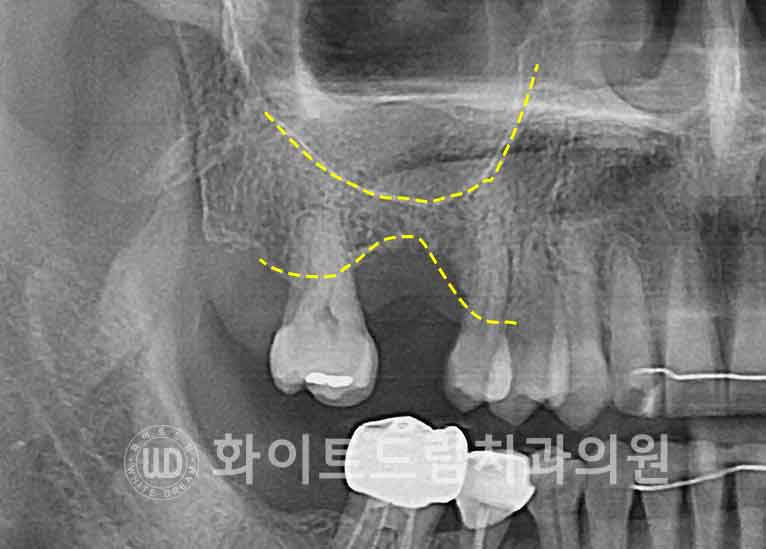

수술 시, 측방부에 작은 골창(window)을 형성한 뒤

상악동막을 조심스럽게 들어 올리고,

그 공간에 골이식재를 주입하여

부족했던 치조골 높이를 보강했습니다.

이 상악동거상술, 잘 됐는지 어떻게 확인하나요?

우선 엑스레이(X-ray) 상으로는,

이식된 골이 상악동저를 따라 매끄럽고 둥근 형태의

‘동산 모양’(dome shape)으로 형성되어 있는지를 확인합니다.